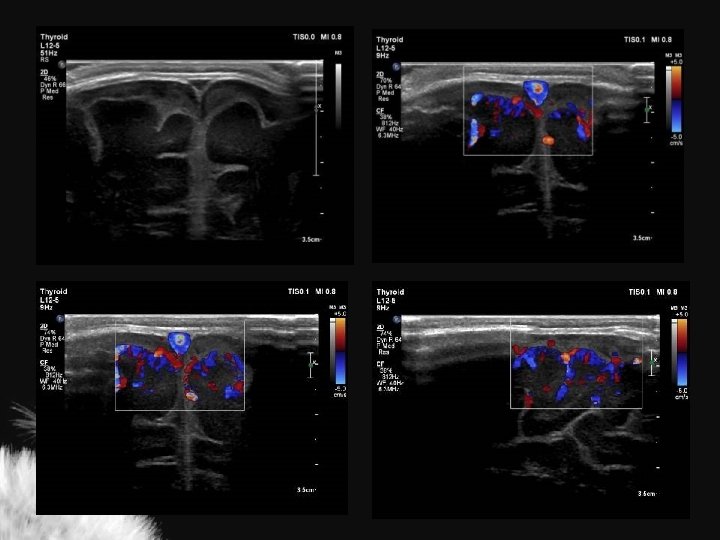

Artérias cerebrais normais

Valores normais ACI ACA AB Vs (cm/s) 50 + 15 42 + 15 41 + 16 Vd (cm/s) 11 + 4 11 + 5 11 + 4 TAMX (cm/s) 22 + 6 21 + 9 19 + 7 0, 77 + 0, 08 0, 73 + 0, 08 0, 72 + 0, 09 RI Deeg KH. Neuroradiology 32: 60 -63

Índice de resistência (IR) nas artérias intracranianas ACA ACI Martin (1982) 0, 75 + 0, 03 Jorch (1986) 0, 74 + 0, 06 Lipman et al. (1982) 0, 79 + 0, 04 Perlman et al. (1985) 0, 66 + 0, 06 Deeg (1989) 0, 73 + 0, 08 AB 0, 77 + 0, 07 0, 73 + 0, 06 0, 77 + 0, 08 0, 72 + 0, 09 ACA artéria cerebral anterior, ACI artéria carótida interna, AB artéria basilar IR pré-termo 0, 79 + 0, 02 IR > 2 anos 0, 50 + 0, 08